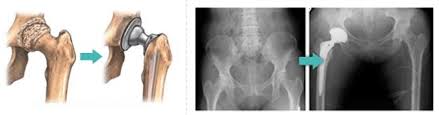

- 고관절 전치환술(Total Hip Arthroplasty, THA): 골관절염이나 류마티스 관절염, 골절 등에 널리 사용되는 방식으로, 관절 전체를 인공 관절로 교체합니다.